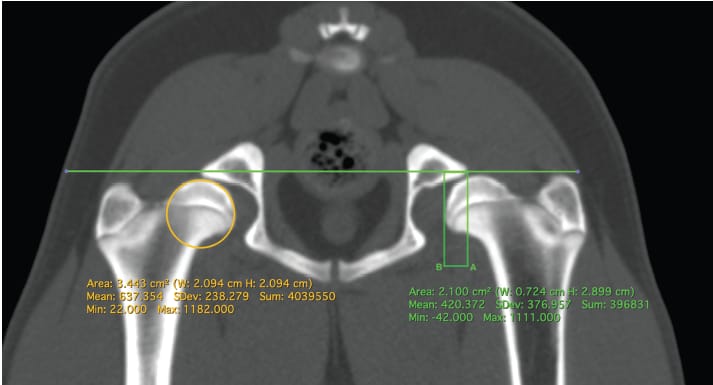

Method of measurement of dorsolateral subluxation (DLS) score. This figure demonstrates the method of measurement of the DLS. 3D

multi-planar reconstruction is used to obtain a transverse image at the lateral-most point of the central dorsal acetabular rim. A line is

drawn connecting the dorsal acetabular rims. The femoral head diameter is measured using a circular tool. Two perpendicular lines are

drawn down from the original line at the level of the medial-most portion of the femoral head (Line A) and the lateral-most portion of the

acetabulum (Line B). The following calculation is performed to obtain the DLS score (distance between Line A and Line B/diameter of the femoral

head) 100.